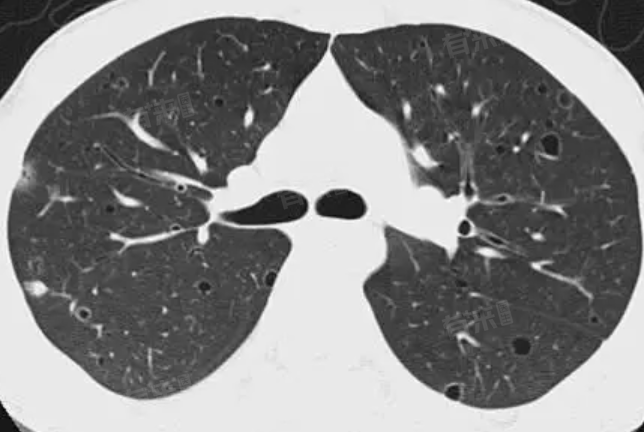

肺部肉芽肿病变是指肺组织内出现的类似结节状的病灶,是由巨噬细胞及其演化的细胞局部浸润和增生所形成,境界比较清楚的结节状病灶。这种病变的原因多种多样,主要包括药物反应、感染、自身免疫性疾病等。